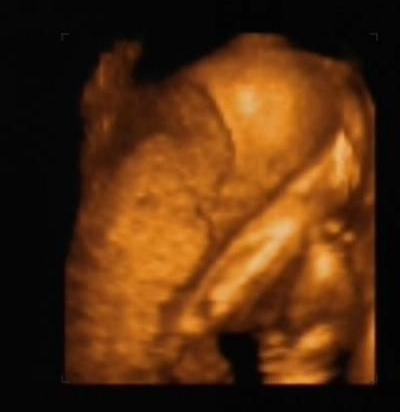

Hagyjatok már!!! (két kéz és egy láb látható a képen, úgy bújt el a drága

)